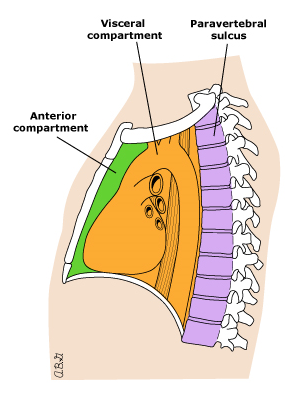

Kəskin mediastinit əksər hallarda ikincili xəstəlikdir, başqa sözlə, döş qəfəsi və ya ətraf orqanlarda baş verən zədələnmə və ya irinli iltihabi xəstəliklərin ağırlaşmasıdır (Şəkil 8).

- Ətraf orqanlarda baş verən irinli iltihabın divararalığına keçməsi nəticəsində baş verən mediastinitlərə də az rast gəlinmir. Plevra və ağciyərin xəstəlikləri (irinli plevrit, abses), boyun, retroperitoneal fleqmona, qabırğaların, fəqərələrin, döş sümüyünün osteomielitləri divararalığına yayıla bilər.